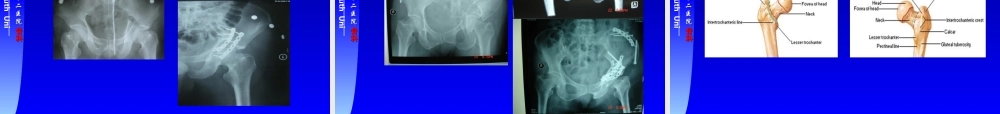

中南大学湘雅二医院中南大学湘雅二医院骨科骨科CentralSouthUniit骨盆骨折和下肢骨折骨盆骨折和下肢骨折pelvicfracturesandpelvicfracturesandfracturesofthelowerextremityfracturesofthelowerextremity中南大学湘雅二医院骨科中南大学湘雅二医院骨科倪江东倪江东中南大学湘雅二医院中南大学湘雅二医院骨科骨科CentralSouthUniitContentsContentsPelvicFracturesPelvicFracturesFracturesofFemoralNeckFracturesofFemoralNeckIntertrochantericFracturesIntertrochantericFracturesFracturesoftheShaftoftheFemurFracturesoftheShaftoftheFemurFracturesoftheTibiaandFibulaFracturesoftheTibiaandFibula中南大学湘雅二医院中南大学湘雅二医院骨科骨科CentralSouthUniitPelvicFracturesPelvicFracturesAnatomy中南大学湘雅二医院中南大学湘雅二医院骨科骨科CentralSouthUniitPelvicFracturesPelvicFracturesAnatomy髂腰韧带骶棘韧带骶结节韧带骶髂关节耻骨联合中南大学湘雅二医院中南大学湘雅二医院骨科骨科CentralSouthUniitPelvicFracturesPelvicFracturesClassificationClassificationLocationofFractureLocationofFractureAvulsionfracturesSacrumandcoccyxfracturesSinglebreaksinthepelvicringPelvicringdisruptions——twoormorebreaksinthepelvicring中南大学湘雅二医院中南大学湘雅二医院骨科骨科CentralSouthUniitPelvicFracturesPelvicFracturesSacrumandCoccyxfractures中南大学湘雅二医院中南大学湘雅二医院骨科骨科CentralSouthUniitPelvicFracturesPelvicFracturesAvulsionfractures髂前上棘撕脱骨折中南大学湘雅二医院中南大学湘雅二医院骨科骨科CentralSouthUniitPelvicFracturesPelvicFracturesSinglebreaksinthepelvicring中南大学湘雅二医院中南大学湘雅二医院骨科骨科CentralSouthUniitPelvicFracturesPelvicFracturesPelvicringdisruptions–twoormorebreaksinthepelvicringAO分型•A型A-1–Fractureofinnominatebone;avulsionA-2–Fractureofinnominatebone;directblowA-3–Transversefractureofsacrumandcoccyx•B型B-1–Unilateralpartialdisruptionofposteriorarch,externalrotation(“openbook”injury)B-2–Unilateral,partialdisruptionofposteriorarch,internalrotation(lateralcompressioninjury)B-3–Bilateral,partiallesionofposteriorarch•C型C-1–Unilateral,completedisruptionofposteriorarchC-2–Bilater...